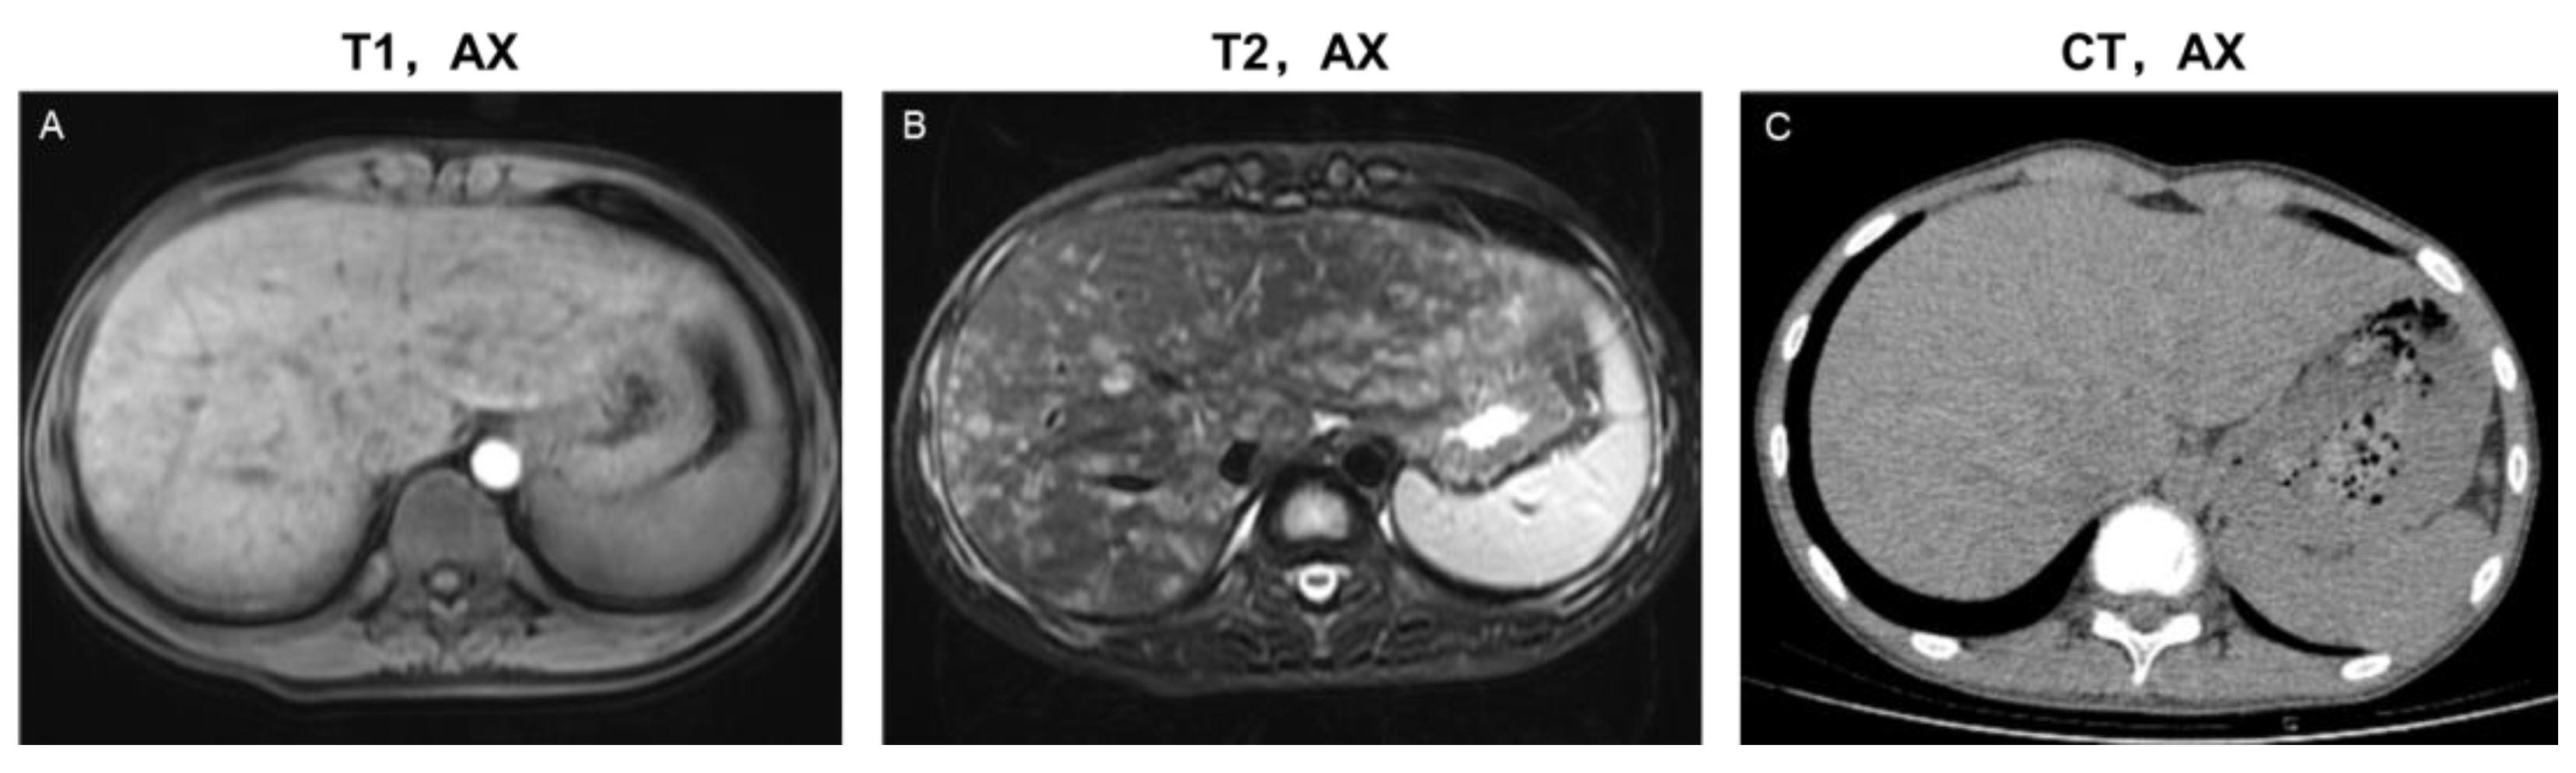

3.3.1. Parenchymal Lesions

- Evolution of parenchymal lesions in eight patients with multiple MRI scans